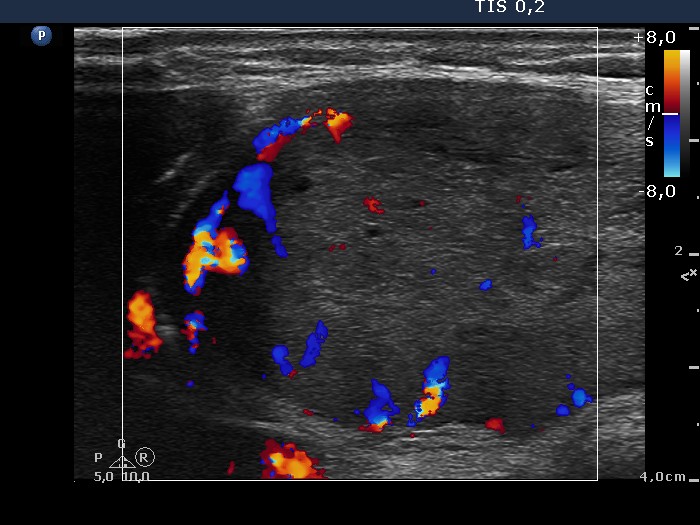

Ultrasonography. The thyroid was echonormal and presented several discrete hypoechogenic lesions. There was a large moderately hypoechogenic nodule in the isthmus. The nodule did not display halo but did perinodular blood flow.